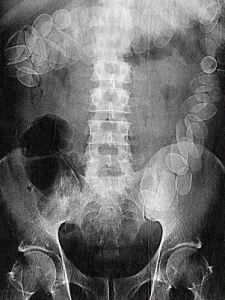

Bolletjesslikkers

'Iedere week,' signaleert chirurg F. van der Heijden van het Amsterdamse Onze Lieve Vrouwe Gasthuis, 'komt op de afdeling spoedeisende hulp wel een patiënt binnen die niet van zijn ingeslikte cocaïnebolletjes afkomt.'

Op hun tocht door het verteringskanaal komen de bolletjes twee belangrijke obstakels tegen. Tussen de maag en de twaalfvingerige darm bevindt zich een kringspier, de maagportier, die voedsel doorlaat naar de dunne darm. Een tweede barrière is een klep, de klep van Bauhin, op de plaats waar de dunne darm overgaat in de dikke darm.

Vorig jaar overleed één smokkelaar in het Gasthuis aan een overdosis en onlangs werd een patiënt blind nadat een bolletje was geknapt. Als dat gebeurt, komt zo'n 100–500 mg cocaïne in het bloed, waardoor vaten verkrampen en de bloeddruk snel stijgt. Dat kan weer leiden tot een hersen- of hartinfarct.

Andere symptomen zijn epileptische aanvallen en hallucinaties. Voor de meeste mensen, die gemiddeld 5 L bloed hebben, is 200 mg fataal.

Er wordt met een röntgenfoto vastgesteld waar de bolletjes zich bevinden (zie afbeelding).

Waar bevinden zich de meeste bolletjes?